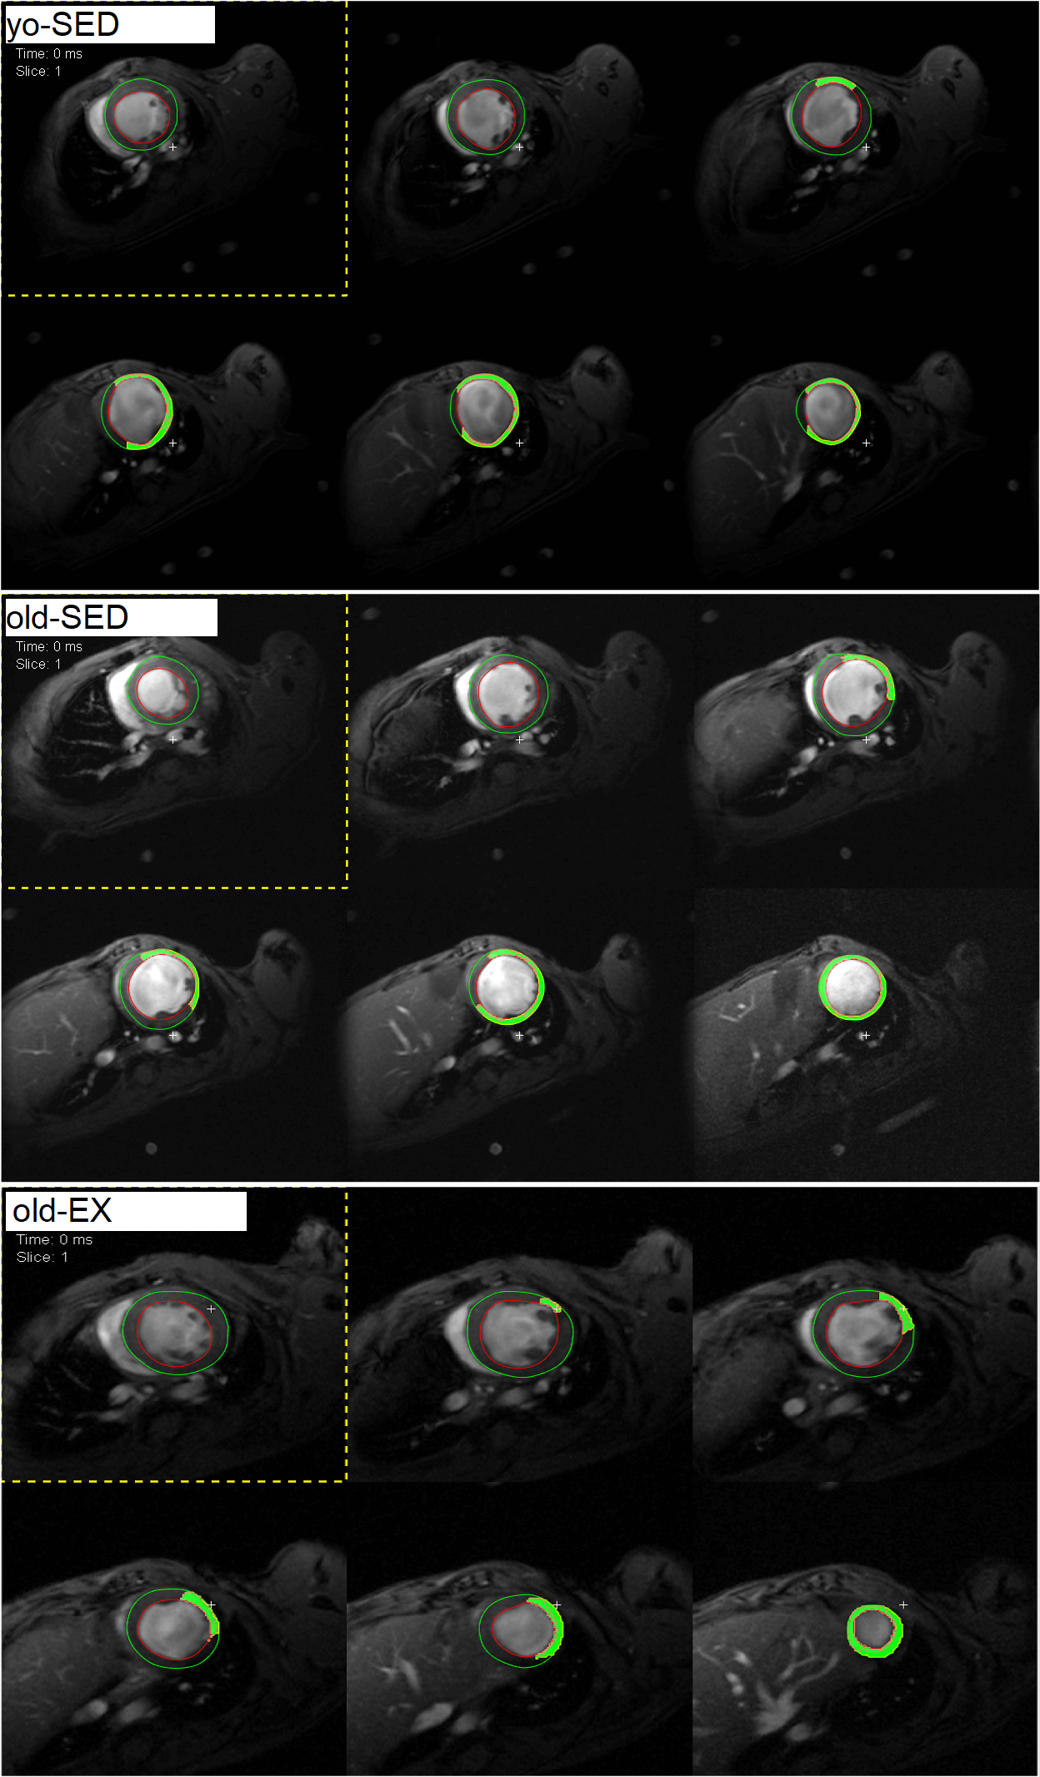

Abb.1: Enddiastolische Kurz- und Längsachsen. Quelle: Autor/Segment (http://segment.heiberg.se).

Im Anschluss an das Trainingsprotokoll erfolgte die mikrochirurgische Induktion eines Herzinfarkts durch permanente Okklusion des Ramus interventricularis anterior (RIVA). An Tag 28 nach Infarktinduktion erfolgte eine kardiale MRT, um die Funktion und Morphologie zu messen. Die MRT-Daten wurden mit der frei verfügbaren Software Segment (http://segment.heiberg.se) analysiert. Segmentierung, Funktionsmessungen des linken Ventrikels, sowie Strain- und Narbenmessungen erfolgten semi-automatisch. Die statistische Auswertung erfolgte mittels SigmaPlot 13.0.

Die enddiastolische Wanddicke des linken Ventrikels war sowohl im Infarkt-Areal als auch im gesunden Vergleichsareal bei der old-EX-Gruppe signifikant größer als in den Gruppen yo-SED und old-SED (Abb. 2).